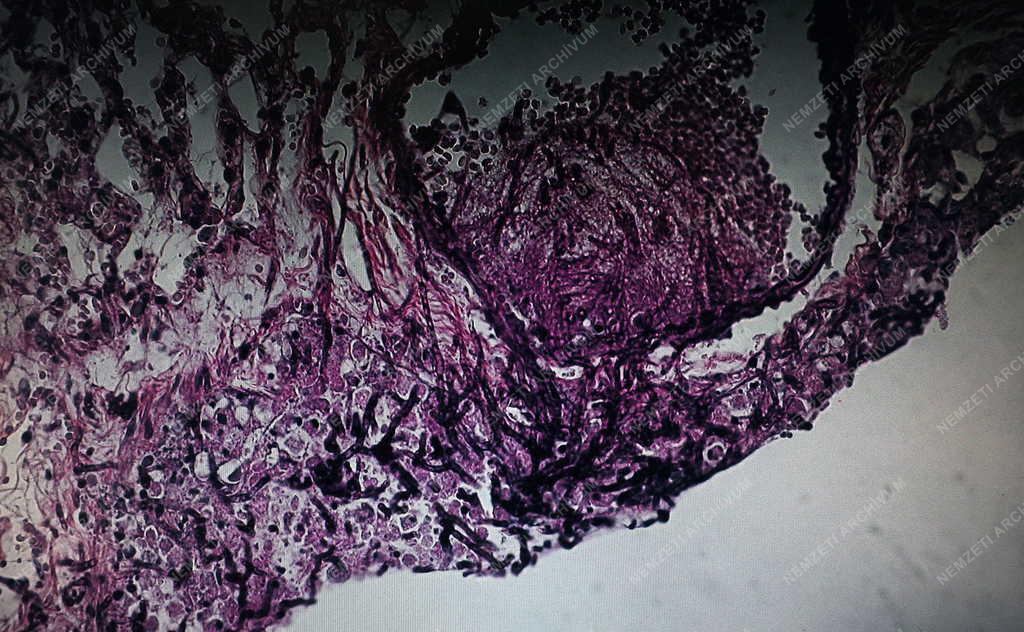

Patogén gombafonalak egy állatkísérletből származó tüdőszövetben. A Debreceni Egyetem Biotechnológiai és Mikrobiológiai Tanszékén sikeres kísérleteket végeznek a PAF /Penicillum chrysogenum/ gomba által termelt gombaellenes fehérjével. A sikeres állatkísérletek után 4-5 év múlva készülhet olyan hatóanyag, gyógyszer, ami segít a legyengült, immunhiányos emberi szervezet megóvásában.